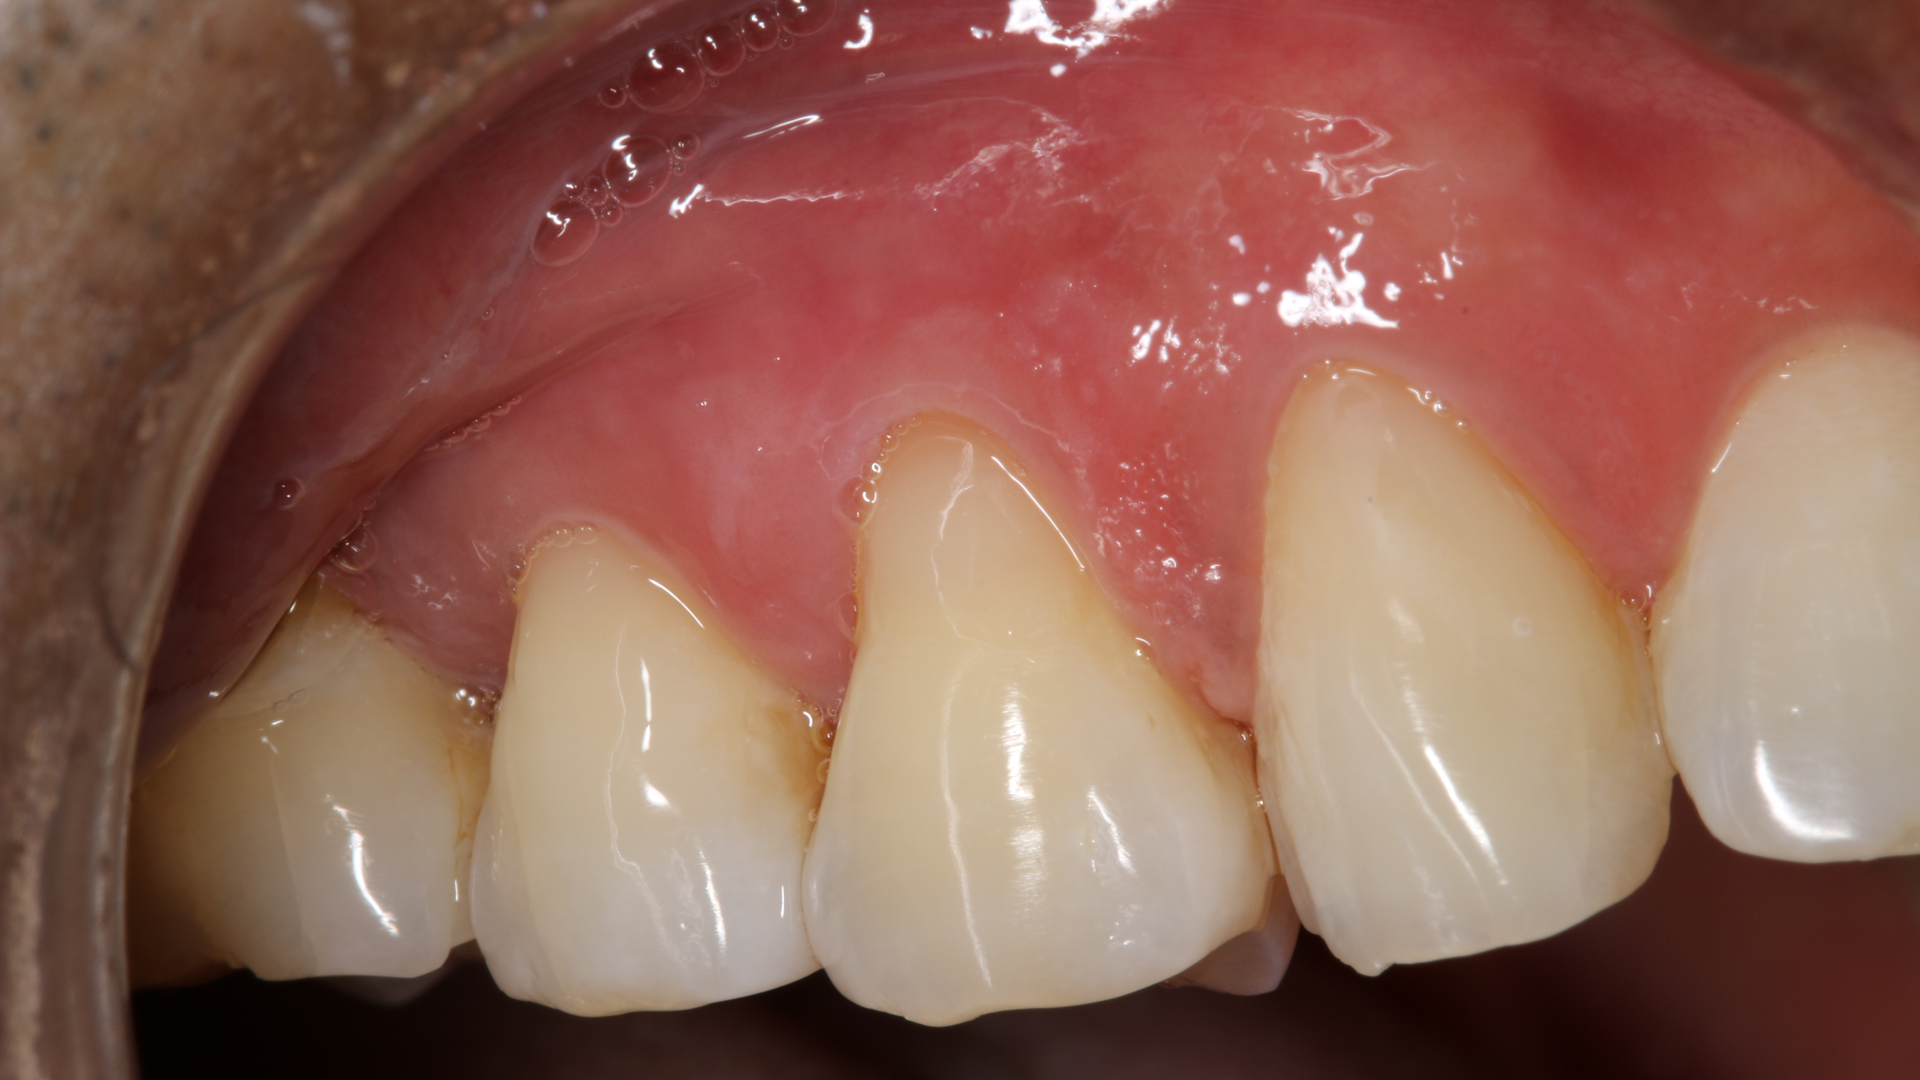

A 45-year-old male presented for three class V fillings. Teeth nos. 4 and 5 had cervical abrasions (or erosion), and no. 6 had a defective existing composite fillingThe teeth to be restored in this case had excellent gingival health, and the patient was in good health. The patient was anesthetized with one carpule (1.7 ml) of lidocaine with 1:100,000 epinephrine.

From the one- and one-and-a-half year postoperative images, we can analyze the longevity performance of the restorations. The restorations have proven to be color-stable and retain their polish and structural integrity (figures 5 and 6).References